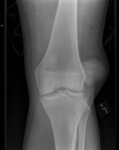

Joint dislocation

Left knee radiograph demonstrating lateral patella dislocation